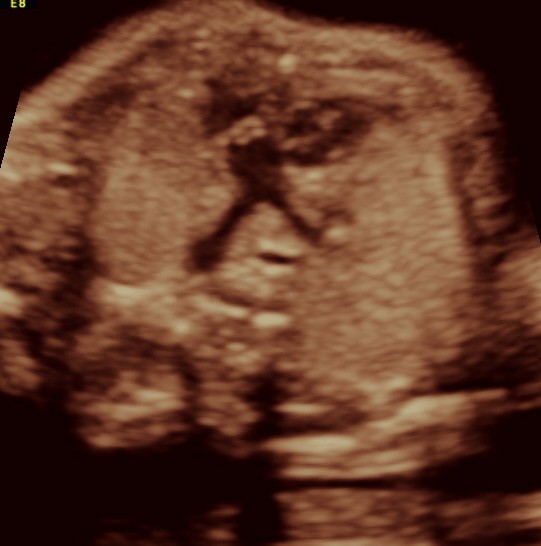

vsd is seen in the picture below.

the following 3 D reconstructed image shows the parallel flow of the great arteries